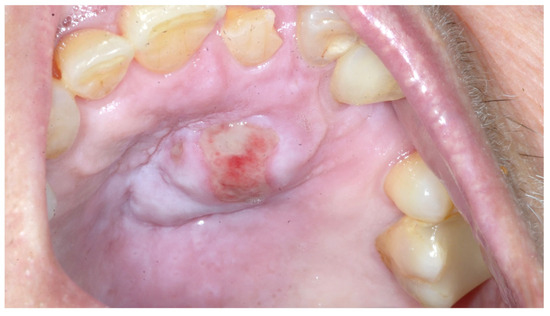

The intricacies of disorders of the oral cavity, head, and neck present clinicians with significant challenges, necessitating a multidisciplinary approach to achieve accurate diagnosis and effective therapeutic strategies. This Special Issue aims to explore the spectrum of complex cases encountered in these anatomical regions, encompassing diverse etiologies, diagnostic dilemmas, and therapeutic interventions. By delving into nuanced clinical scenarios, this collection seeks to foster a deeper understanding of the complexities that are inherent to managing conditions ranging from oral cancers and maxillofacial trauma to rare pathologies and treatment-resistant diseases. Through case presentations, innovative diagnostic techniques, therapeutic modalities, and outcome assessments, this Special Issue endeavors to advance our knowledge and enhance clinical practice regarding disorders of the oral cavity, head, neck. Contributions from clinicians, researchers, and allied healthcare professionals are invited, in order to enrich this exploration and contribute to our collective effort to address the formidable challenges posed by these interlinked clinical scenarios. For this Special Issue, we would particularly like to publish research articles and comprehensive reviews.